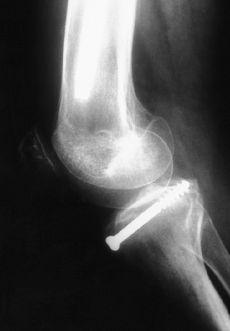

Las fracturas Tipo II, en las que no se consigue una reducción anatómica, deben tratarse quirúrgicamente mediante reducción y osteosíntesis.12,40 Todas las fracturas Tipos III, IV y V deben tratarse mediante reducción quirúrgica y osteosíntesis, habitualmente por artroscopia, empleando suturas, agujas o tornillos, recomendando una inmovilización postoperatoria de 3 semanas y descarga de 6 semanas (Fig. 1). No se recomienda la fijación transepifisaria debido al riesgo de provocar una lesión de la placa fisaria y una deformidad posterior en hiperextensión de la rodilla; para evitarlo algunos autores han recomendado realizar la sutura del fragmento al cuerno anterior del menisco medial o lateral.65

Figura 1. Niño de 14 años de edad con fractura de la espina tibial (Meyers y McKeever Grado III). A: Radiografías preoperatorias. B: Fijación artroscópica con dos tornillos de Whipple. C: Radiografía a las 10 semanas de evolución donde se aprecia consolidación de la fractura.